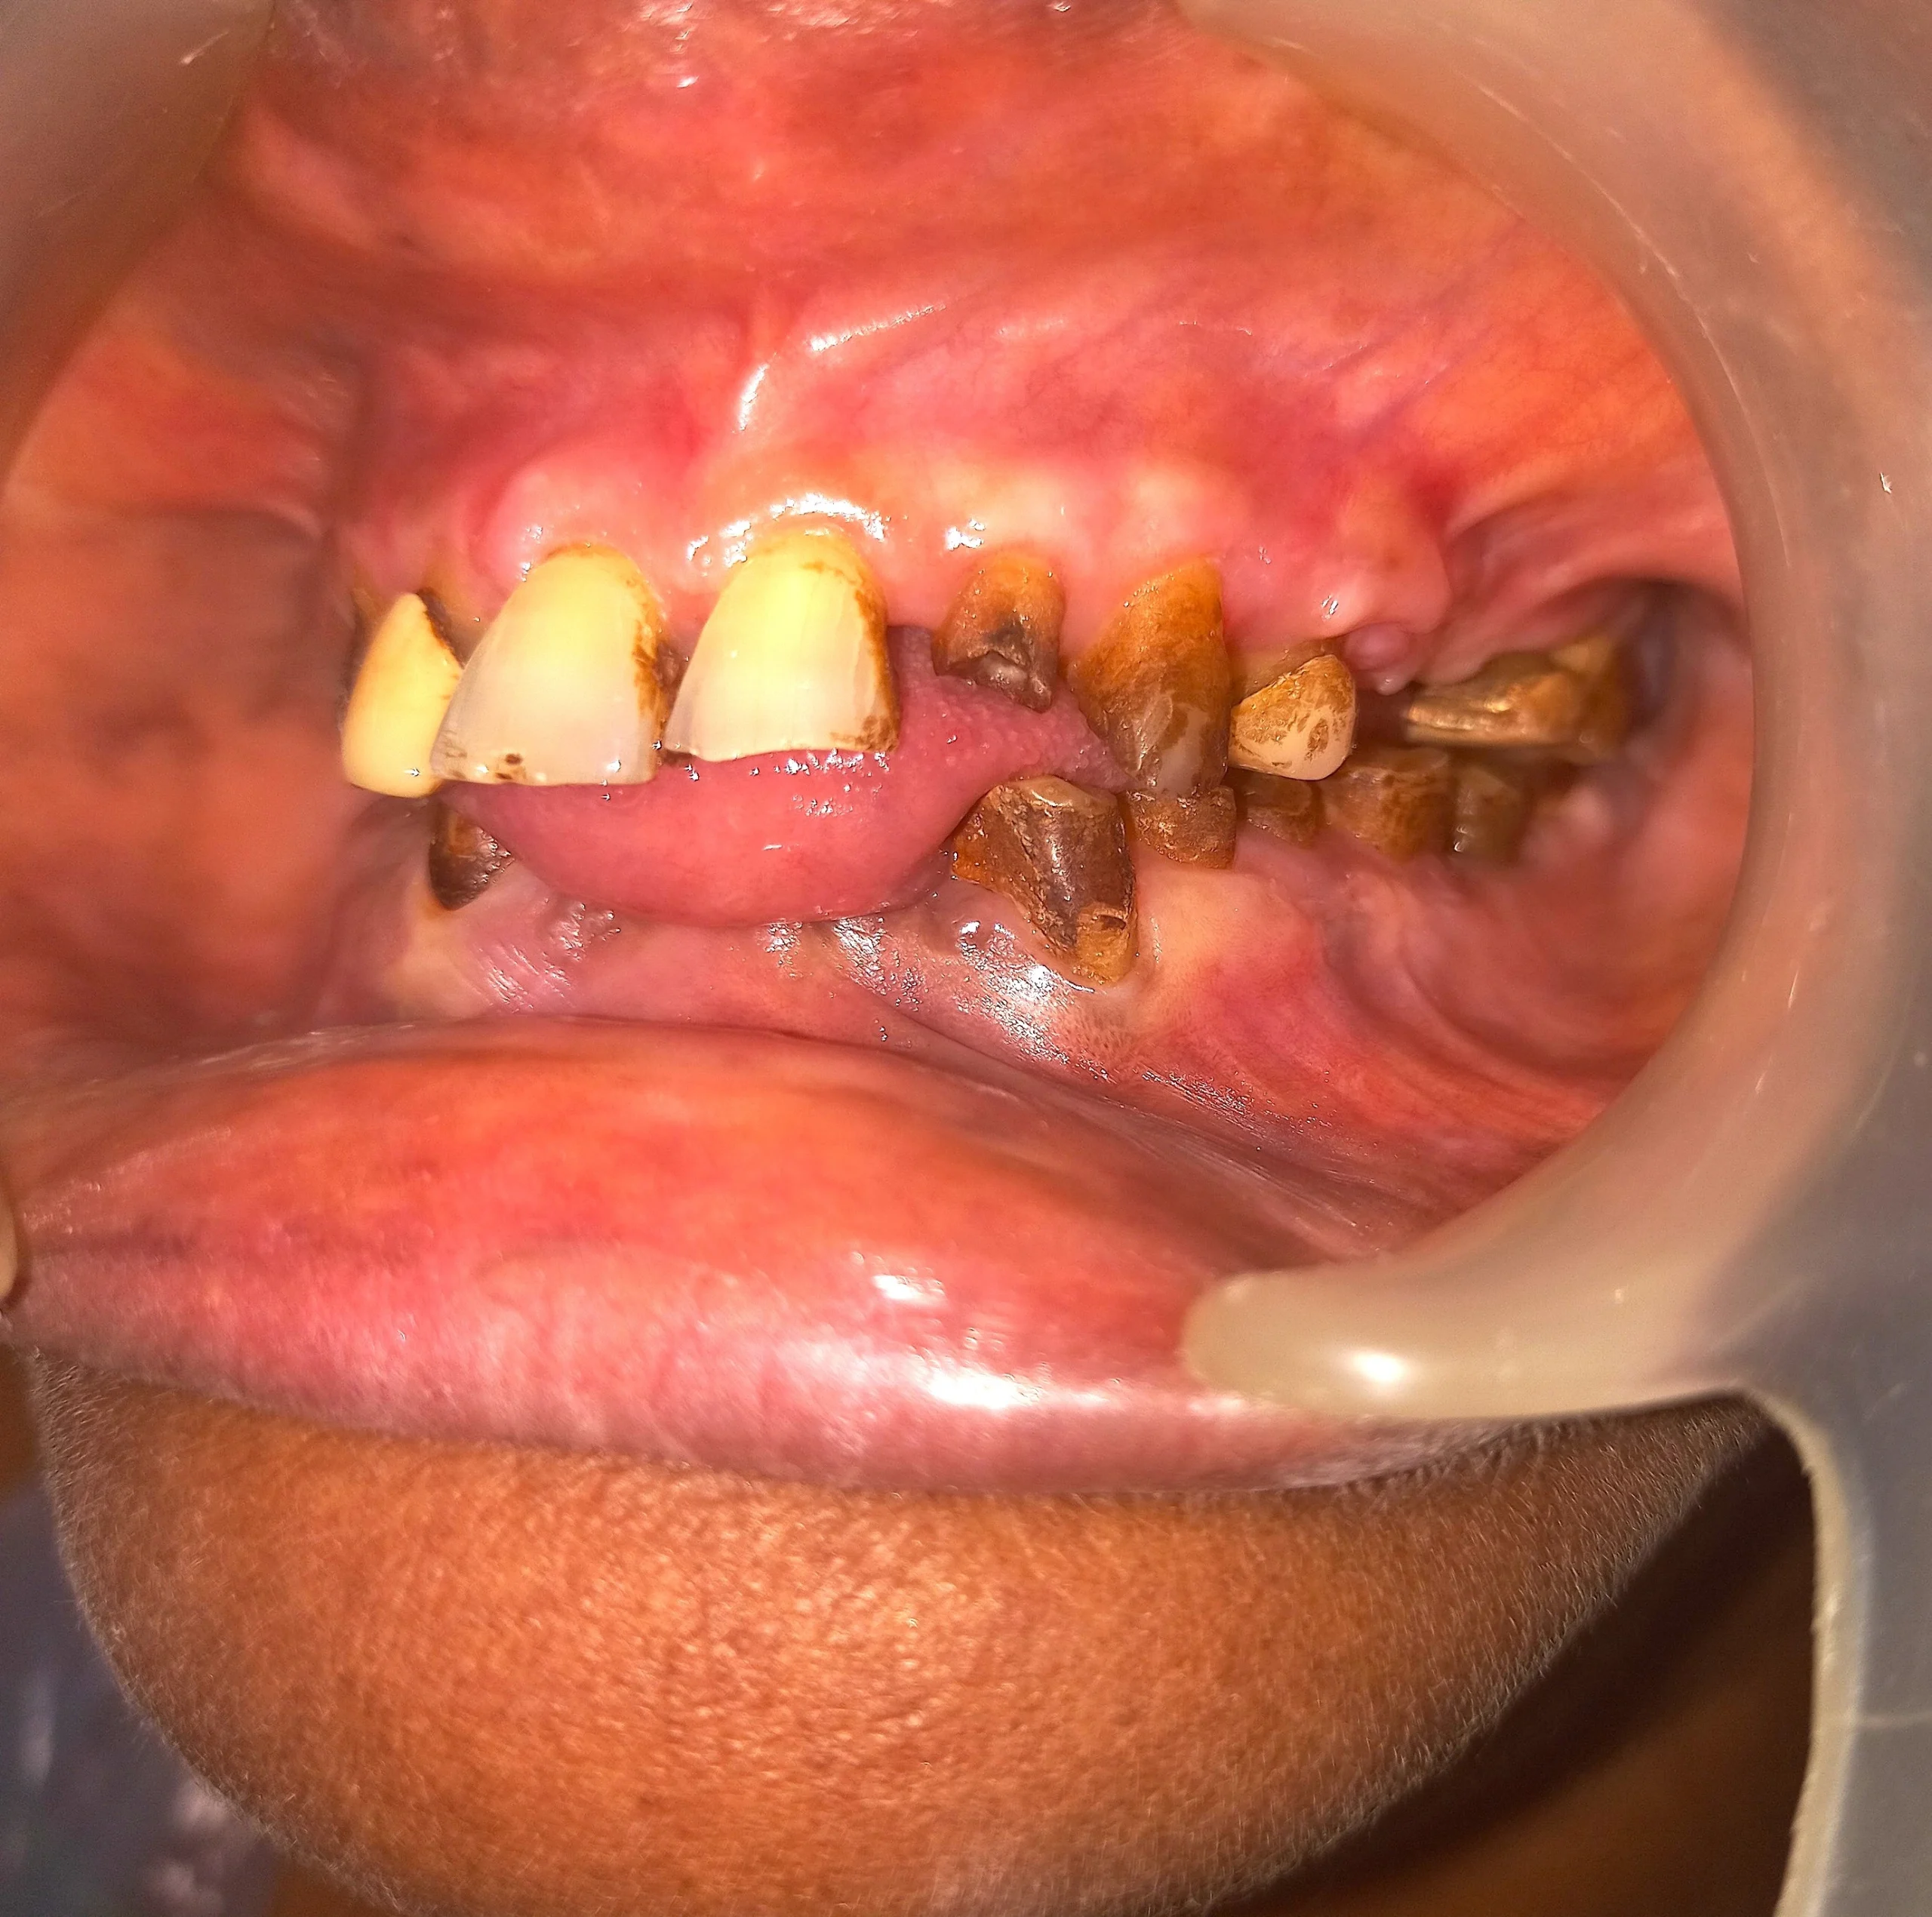

This elderly patient had been chewing supari for many years. Over time, her teeth wore down unevenly, her bite collapsed, and chewing food became extremely difficult.

Facial height reduced, jaw position changed, and daily eating became tiring and uncomfortable.

A gentle, step-by-step Full Mouth Reconstruction plan was created to restore bite height, improve chewing efficiency, and stabilize remaining teeth — without aggressive surgery.

Age is never the deciding factor. Planning, precision, and comfort are.

Completely worn out teeth

Teeth shaping during Full Mouth Reconstruction